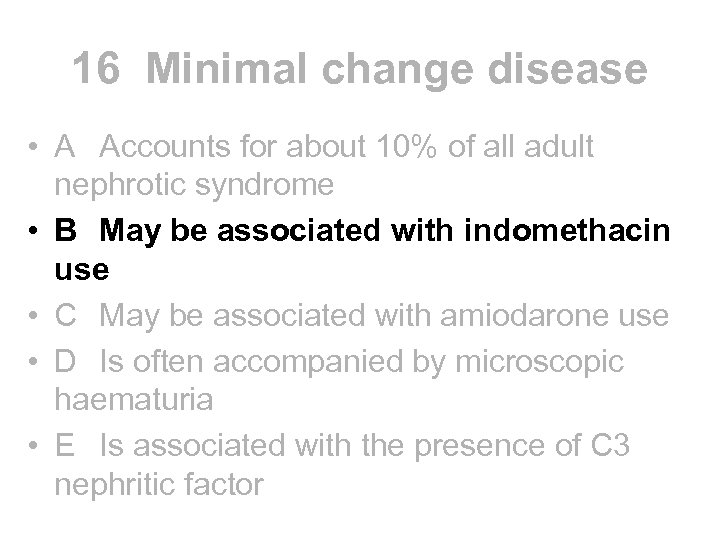

Minimal change nephropathy • Aetiology • - usually idiopathic but can be 2 y to lymphoma or assoc with NSAIDs, gold or lithium (not amiodarone) • Presentation • - nephrotic syndrome accounting for 80 -90% NS in children and 25% in adults (not 10%). Micro haematuria is uncommon • Diagnosis • - biopsy in adults but not usually in children. Not associated with C 3 nephritic factor • Treatment • - usually responds to steroids. Cyclophosphamide and cyclosporin can be used if relapses • Outcome • - remission is common after steroids. CRF extremely unlikely. Often complicated by pneumococcal peritonitis in past

Minimal change nephropathy • Aetiology • - usually idiopathic but can be 2 y to lymphoma or assoc with NSAIDs, gold or lithium (not amiodarone) • Presentation • - nephrotic syndrome accounting for 80 -90% NS in children and 25% in adults (not 10%). Micro haematuria is uncommon • Diagnosis • - biopsy in adults but not usually in children. Not associated with C 3 nephritic factor • Treatment • - usually responds to steroids. Cyclophosphamide and cyclosporin can be used if relapses • Outcome • - remission is common after steroids. CRF extremely unlikely. Often complicated by pneumococcal peritonitis in past